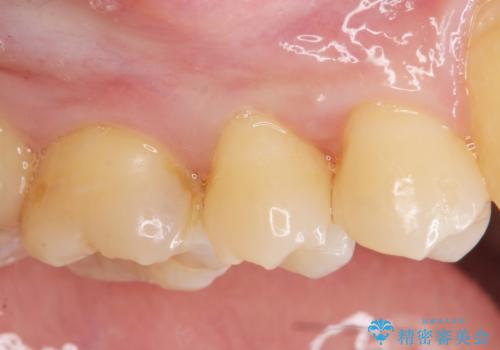

今回の治療では、虫歯を除去したのちより修復に適した素材を選択することで歯を削る量を可及的に少なくすることと、長期的な予後を期待できるような状態にすることができました。

セラミック・ゴールド共に化学的な変化が少なくインレー素材として理想的ですが、色調や強度・加工のしやすさ・最低限必要な厚み等の条件が異なります。